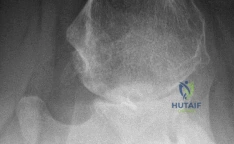

A 2-year-old girl is diagnosed with unilateral developmental dysplasia of the hip (DDH). Radiographs, seen here, show a dislocated left hip with an acetabular index of 45 degrees and evidence of femoral head flattening. Attempts at closed reduction under general anesthesia are unsuccessful.

Option C (open reduction with capsulorrhaphy and possibly femoral shortening osteotomy) is the most appropriate next step. Open reduction addresses the soft tissue impediments to reduction and allows for direct visualization of the femoral head and acetabulum. Capsulorrhaphy stabilizes the hip after reduction. Femoral shortening osteotomy is often required in older children (typically >18-24 months) to reduce tension on the femoral head after reduction, thereby reducing the risk of AVN and facilitating a stable reduction. Addressing the acetabular dysplasia (e.g., with a Dega or Salter osteotomy) may also be necessary at the time of open reduction or as a staged procedure, depending on the residual dysplasia after reduction.